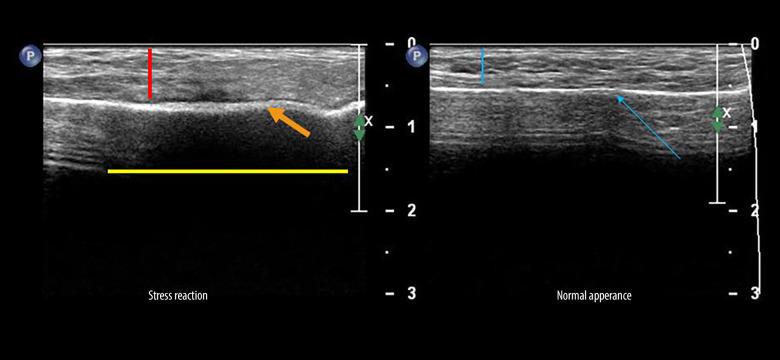

Medical imaging tests are widely used to diagnose a broad spectrum of lower-limb injuries. Among these modalities, ultrasound (US) imaging has gained significant traction as a valuable diagnostic instrument for assessing conditions primarily affecting muscles, tendons, ligaments, and other soft tissues. However, there are important dilemmas related to the indications and possibilities of US in lower-limb injuries. Conflicting findings and approaches raise questions regarding the validity, accuracy, and usefulness of the US in that area. This narrative review attempts to summarize the current state of knowledge regarding US imaging of lower-limb injuries. The study provides a detailed discussion of the existing literature and contemporary insights on the diagnosis of lower-limb injuries using US examination, and draws attention to the role of the US in interventional procedures and monitoring of the healing process. The characteristics of normal muscles, tendons, and ligaments in US imaging are presented, along with the most commonly documented conditions affecting these tissues. Furthermore, the benefits and justifications for employing US in interventional procedures are discussed, ranging from platelet-rich plasma injections to physiotherapeutic treatments like percutaneous electrolysis. The study was further augmented with US pictures depicting various lower-limb injuries, mainly affecting young athletes. This article aims to review the role of US imaging in the diagnosis and management of common lower-limb injuries.

医学影像学检查广泛用于诊断各种下肢损伤。在这些方法中,超声(US)成像作为一种评估主要影响肌肉、肌腱、韧带和其他软组织的疾病的有价值的诊断工具,已经得到了广泛的应用。然而,US 在下肢损伤中的适应证和可能性存在一些重要的难题。相互矛盾的发现和方法使得 US 在该领域的有效性、准确性和实用性受到质疑。本叙述性综述旨在总结目前关于 US 成像在下肢损伤中的应用的知识状况。该研究详细讨论了现有的文献和关于使用 US 检查诊断下肢损伤的最新观点,并提请注意 US 在介入程序和愈合过程监测中的作用。本文介绍了 US 成像中正常肌肉、肌腱和韧带的特征,以及最常见的影响这些组织的疾病。此外,还讨论了 US 在介入程序中的应用的益处和理由,从富含血小板的血浆注射到经皮电解等物理治疗。本文还进一步增加了描述各种下肢损伤的 US 图片,主要影响年轻运动员。本文旨在综述 US 成像在常见下肢损伤的诊断和治疗中的作用。